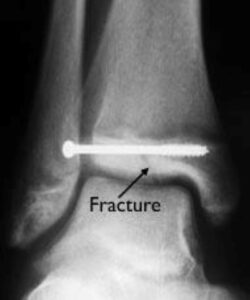

The severity of ankle fractures in children can vary widely. Minor fractures are often effectively treated with a simple walking boot, while complex fractures may necessitate surgical intervention. A pediatric orthopedic specialist will guide you through the available treatment options and provide ongoing follow-up care to ensure proper healing and monitor long-term recovery outcomes.

In children and adolescents, ankle fractures typically affect the tibia or fibula, often involving the growth plates—specialized areas of cartilage near the ends of long bones. Growth plates play a critical role in bone development, gradually hardening into solid bone as the child matures. However, because these growth plates are the last parts of the bones to solidify, they are particularly prone to injury and fractures. As adolescents approach the end of their growth phase, growth plates begin to close and harden, making them susceptible to transitional fractures during this maturing stage. Two common types of transitional ankle fractures are triplane fractures and Tillaux fractures, which require specific treatment approaches depending on their severity and location (refer to the Treatment section for more details)